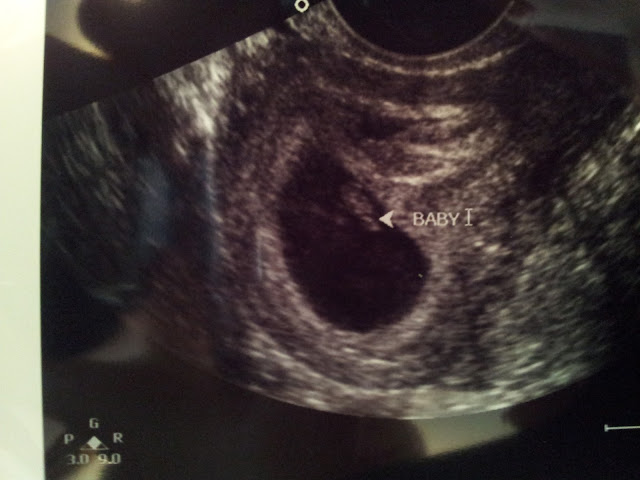

We had our first ultrasound at week 6.5 and we got to see the little nugget (looks more like a blob but it's a baby I promise). We got to see the blood pumping and even got to hear the heartbeat! It was very cool and exciting. Here is the first look at baby!

| Ultrasound 6.5 weeks |